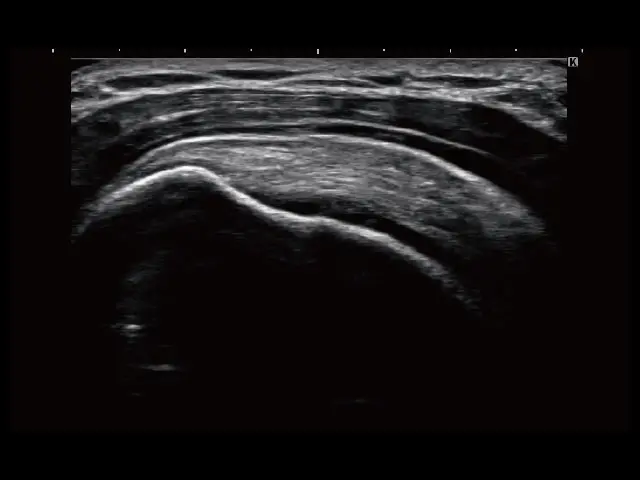

イメージギャラリー

イメージ画像を表示する